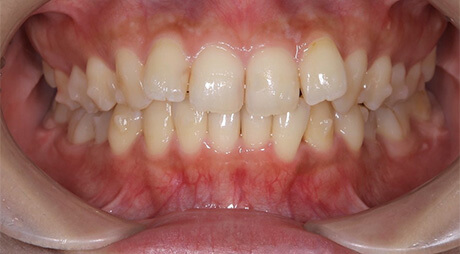

- Before

上の前歯の古い被せ物を治したいと言うことで来院されました。上下の前歯は少しガタガタになっており、奥歯には古い金属の詰め物が見られます。